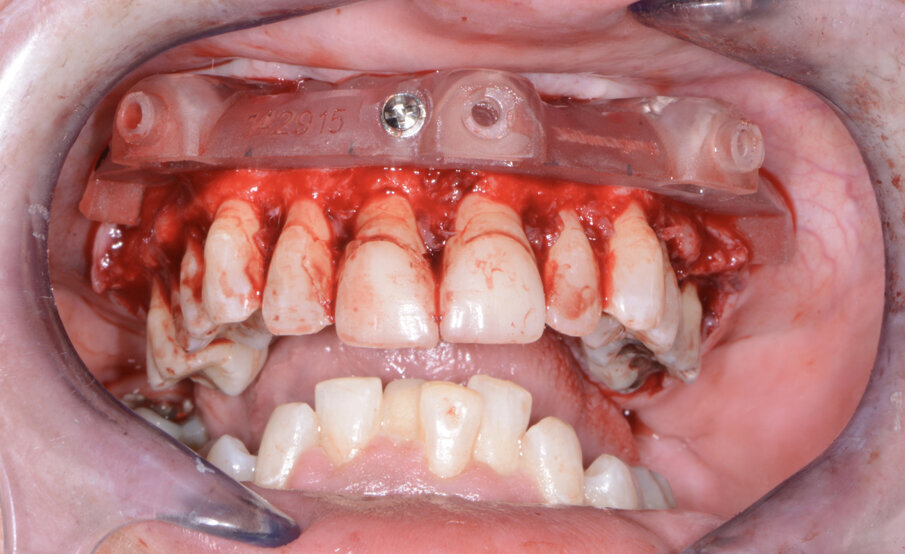

Once the virtual plan had been orchestrated and fully confirmed, the next appointment was for the planned surgery with all the necessary components for the guided surgical approach. The patient was appropriately sedated with intravenous medications, and local anaesthesia was administered in both arches. The tissue was then reflected using the Reflector instrument (GoldenDent) so that the bone levelling surgical guide would be fully seated and fixed with its respective retention screws (Fig. 7). After the positioning of the surgical guide, the maxillary teeth were atraumatically extracted utilising the Physics Forceps (GoldenDent). Once the appropriate bone levelling had been accomplished with the surgical handpiece, the implant surgical guide (Fig. 8) was positioned into the bone levelling guide and the osteotomies for the implants were initiated with a designated pilot drill in the implant system’s guided surgery drill kit (Adin Dental Implant Systems; Fig. 9). Using precise orientation, depth and direction, the guided surgery kit provides fast, effective and predictable preparation and placement of dental implants for dental practitioners. It also features easy-to-follow layouts along containing self-centring drills with built-in stoppers. The unique design of the guide, employing ActiveFlow irrigation technology, directs cooling saline through the guide, ensuring that irrigation reaches the bone and thereby reducing the possibility of bone heating throughout the procedure.

The prefabricated immediate provisional arch restorations with pre-drilled access openings were inspected before being tried in.

The maxillary provisional restoration was tried in to verify a passive fit over the temporary abutments. Once fit had been confirmed, trimmed dental dam pieces were placed to avoid the restoration (Fig. 11) from locking on during the relining procedure with REBASE III FAST set hard reline material (Tokuyama Dental). After the material had polymerised, the immediate provisional restoration was removed and any access material was removed with the Torque Plus laboratory handpiece (Aseptico) and an acrylic bur (Komet). The same procedures were accomplished in the mandibular arch (Figs. 12–14). Once trimmed and polished, the provisional restorations were seated and tightened with a torque wrench at 15 Ncm (Fig. 15). The access openings were filled in three-quarters of the way with Teflon tape, followed by Cavit filling material (3M ESPE). A postoperative panoramic radiograph was taken immediately after the surgery (Fig. 16).